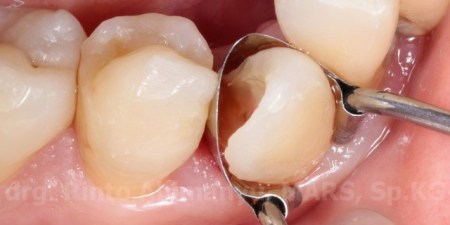

Pemakaian matriks pada pembuatan artificial wall

Matriks yang saya pakai adalah saddle matrix dengan spring clip, matriks ini cukup murah dan mudah penggunaannya… sejawat harus punya nih.. cieee promosi 😛